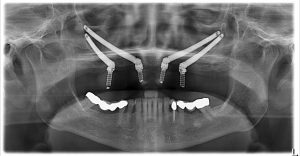

همچنین در شدیدترین موارد تحلیل استخوان، ایمپلنت های چهارتایی زیگوماتیک ارائه داده می شوند. معمولاً این بیماران مدت طولانی بدون دندان بوده اند. با ایمپلنت های چهارتایی زیگوماتیک، به جای دو ایمپلنت زیگوماتیک، چهار ایمپلنت زیگوماتیک در هر فک قرار داده می شود.

ایمپلنت های پتریگوئید Pterygoid در محل اتصال استخوان فک بالا قرار می گیرند و معمولاً ۱۲ تا ۲۰ میلی متر طول دارند. آنها اغلب در ترکیب با ایمپلنت های زیگوماتیک برای ایجاد ثبات بیشتر استفاده می شوند. ایمپلنت های زیگوماتیک که در استخوان گونه قرار می گیرند، را می توان با میله های پرچم مقایسه کرد. درست مانند میله پرچم که برای ثابت ماندن در بادهای شدید به تکیه گاه نیاز دارد، ایمپلنت های زیگوماتیک برای ثبات بهینه به اتصال به ایمپلنت های دیگر نیاز دارند. بدون این اتصال، نوک ایمپلنت زیگوماتیک ممکن است حرکت جزئی داشته باشد.

در مواردی که بیماران استخوان محدودی در دسترس دارند، می توان از ایمپلنت های پتریگوئید استفاده کرد زیرا ممکن است نواحی مناسبی برای ایمپلنت های استخوانی سنتی وجود نداشته باشند. ایمپلنت های پتریگوئید در استخوان قشری متراکم موجود در ناحیه دندان عقل فک بالا، که به عنوان صفحه پتریگوئید شناخته می شود، تکیه داده می شوند. با اتصال ایمپلنت های پتریگوئید به ایمپلنت های زیگوماتیک، یک پایه بسیار پایدار ایجاد می شود که می تواند به طور مؤثر از پروتز ثابت پشتیبانی کند.